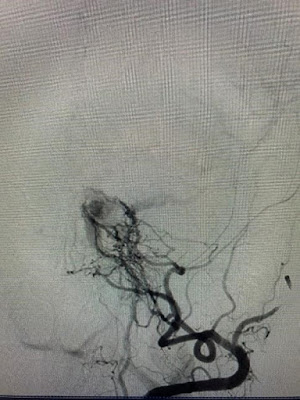

Hình ảnh động mạch cảnh trước can thiệp (trên) và sau can thiệp (dưới)

ThS. BS. Phạm Định Chương – Khoa Nội Thần kinh, BV Hoàn Mỹ Sài Gòn cho biết “Ở trường hợp này, bác sĩ đã tư vấn cho người bệnh và gia đình về tình trạng bệnh, phương pháp điều trị đó là can thiệp nội mạch tắc rò động mạch cảnh xoang hang bằng coil (vòng xoắn kim loại). Đây là một phương pháp điều trị hiện đại, xâm lấn tối thiểu, mang lại hiệu quả cao với thời gian nằm viện ngắn. Với phương pháp này, chúng tôi sẽ đưa một vi ống thông rất nhỏ đến tiếp cận vị trí rò, sau đó đặt các vòng xoắn kim loại (coil) để tắc các vị trí rò. Từ đó giúp cải thiện các triệu chứng của người bệnh”